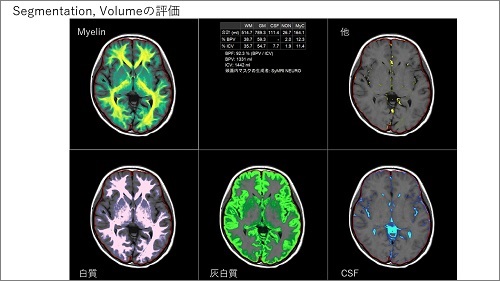

頭部/頭頸部領域における、SmartSpeed AI の様々な臨床応用をご紹介いただきました。藤間先生が最近出版された 3 つの論文を引用されながら、SmartSpeed AI を脳 MRA、頭頸部 3D T1 強調画像、頭頸部 DWI(W.I.P)に対して適用した様々な画像を提示されました。SmartSpeed AI は、従来の Compressed SENSE 再構成や院内の他の 3T 装置と比較しても優れており、撮像の高速化と高画質化の双方で大変有用であると強調されました。

次に、SmartSpeed AI に対して、AI による超解像やリンギングアーチファクト除去も加えた技術(W.I.P)についてもご紹介されました。このような Dual type AI 再構成は、画質の高精細化によって、より詳細な画像評価が可能にすると述べられました。また、Single-shot 撮像に対して超解像を組み合わせることで、コントラストが良好な全脳高精細 T2WI 撮像を、たった 7 秒の撮像で達成できると紹介されました。このように、超解像技術を撮像時間短縮に応用するアプローチは、今後脳のルーチン検査を 1 分台まで短縮する可能性を持ち、会場でも大変話題になりました。